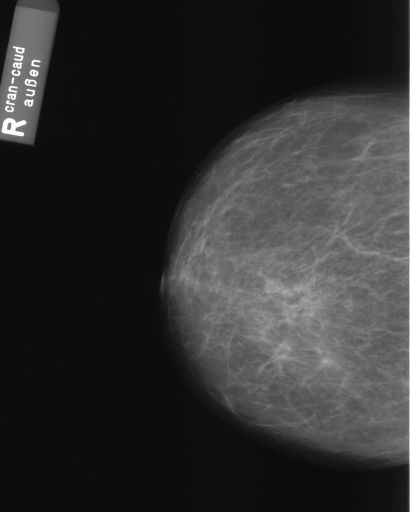

In this section, we report two series of experiments. The first one verifies the correctness or reliability of the micro-DE algorithm to find optimal projections compared to an exhaustive search when we are looking for 4 optimal projection angles out of 16 equidistant angles. In the second experiments, we still provide the results for exhaustive 4/16 selection but examine the evolutionary approach to get 4/180 and 8/180 to investigate the reconstruction accuracy of the micro-DE via correlation of the input image and the reconstructed image using 4/16 (exhaustive), 4/180 (micro-DE) and 8/180 (micro-DE). To conduct the experiments we used 50 images from IRMA dataset [34, 35], a benchmarking collection of 14,400 x-rays images. We selected 10 random classes out of 58 classes, and for each class, we randomly drew 5 images to be used in our experiments. Figure 4 shows the images we have used.

In this series of experiments, we randomly selected three categories from IRMA dataset (namely, breast, foot and lung), and for each category we choose 5 random images from that class (Figures 5, 6 and 7 show these images). When we find “4 out of 180” (4/180) and “8 out of 180” (8/180) projections via micro-DE (tasks that cannot be performed via brute-force), then the question is what can we say about the reconstruction error, in terms of correlation between original and reconstructed images, when we compare evolutionary approximation with the case that we can manage via exhaustive search, namely “4 out of 16” (4/16)? Can micro-DE reach at least the same correlation (similarity) as the brute-force case in lower dimensions? If yes, we may have more confidence in using micro-DE in practice where we cannot apply brute force for benchmarking or direct use, especially for higher dimensions (i.e., the number of projections).